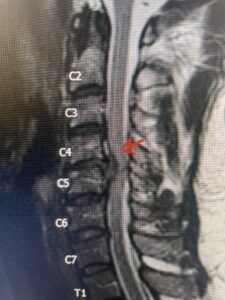

Fig 2a Sagittal and axial T2 weighted cervical MRIs demonstrating large C4 5 herniated disc with spinal cord compression red arrows

Fig. 2a Sagittal T2-weighted cervical MRI demonstrating large C4-5 herniated disc with spinal cord compression (red arrow)

This 47-year-old male who four months prior was lifting weights developed sharp pain in his neck. After that he developed progressive numbness in his arms, neck pain and headache. He said that the right arm was worse than the left. On examination the patient had long tract weakness on the right side which included his triceps, finger extensors, hip flexors, and dorsiflexors. The patient did not have hyperreflexia. MRI (Fig. 2) demonstrated a massive, extruded disc herniation with severe cord compression. The patient because of progressive myelopathy and spinal cord compression was indicated for anterior cervical discectomy and fusion at C4-5 (Fig. 3). Patient had significant improvement of weakness and numbness post operatively.